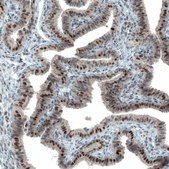

Monoclonal Anti-ATF3 antibody produced in mouse

Prestige Antibodies® Powered by Atlas Antibodies, clone CL1685, purified immunoglobulin, buffered aqueous glycerol solution

immunohistochemistry: 1:50- 1:200

The Human Protein Atlas project can be subdivided into three efforts: Human Tissue Atlas, Cancer Atlas, and Human Cell Atlas. The antibodies that have been generated in support of the Tissue and Cancer Atlas projects have been tested by immunohistochemistry against hundreds of normal and disease tissues and through the recent efforts of the Human Cell Atlas project, many have been characterized by immunofluorescence to map the human proteome not only at the tissue level but now at the subcellular level. These images and the collection of this vast data set can be viewed on the Human Protein Atlas (HPA) site by clicking on the Image Gallery link. We also provide Prestige Antibodies® protocols and other useful information.

- IHC tissue array of 44 normal human tissues and 20 of the most common cancer type tissues.